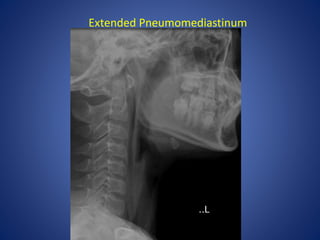

Extended Pneumomediastinum

Retrophyrangeal abscess Extended Pneumomediastinum